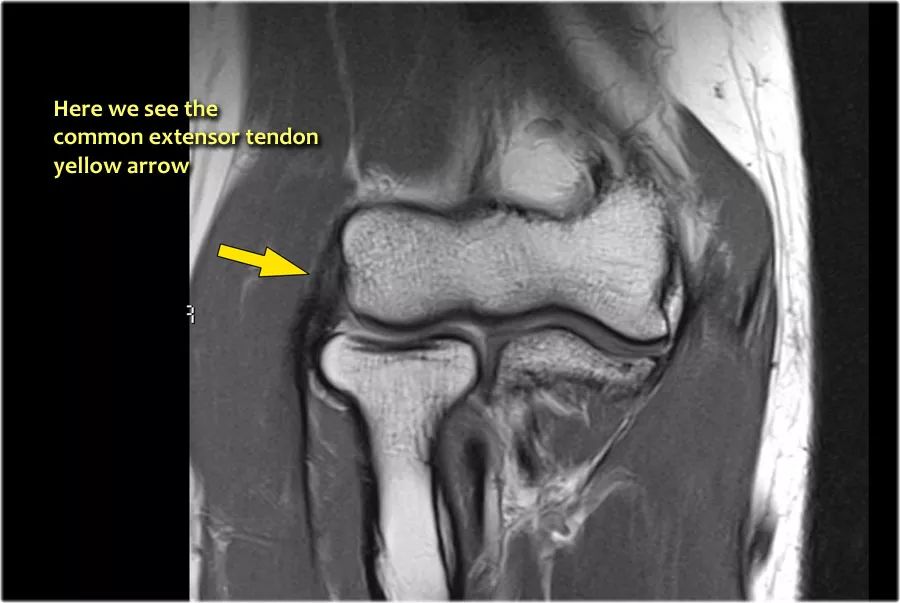

我们可以从连续的冠状位MRI图像观察。

常见的伸肌腱起源于外上髁。在T1W图像上,肌腱应具有低信号强度(黄色箭头)。